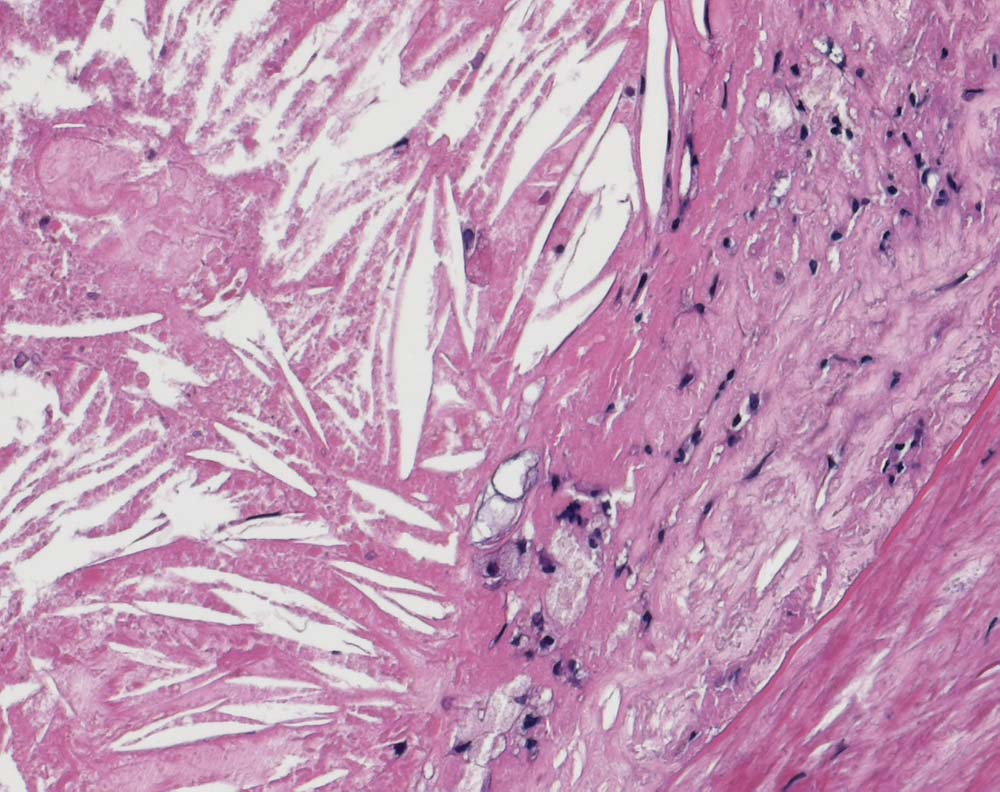

PathoPic ID 9004 - Atherosklerose der Arteria carotis

Atherosklerose der Arteria carotis

vaskulär / Durchblutungsstörung

Arteria carotis

Kardiovaskuläres System

Bildausschnitt aus einem Atherom bestehend aus teils zerfallenen Schaumzellen und wetzsteinförmigen herausgelösten Cholesterinkristallen.

Carotisstenose

Die Cholesterinkristalle entstehen nach dem Zerfall von lipidbeladenen Makrophagen.

Histologie

200